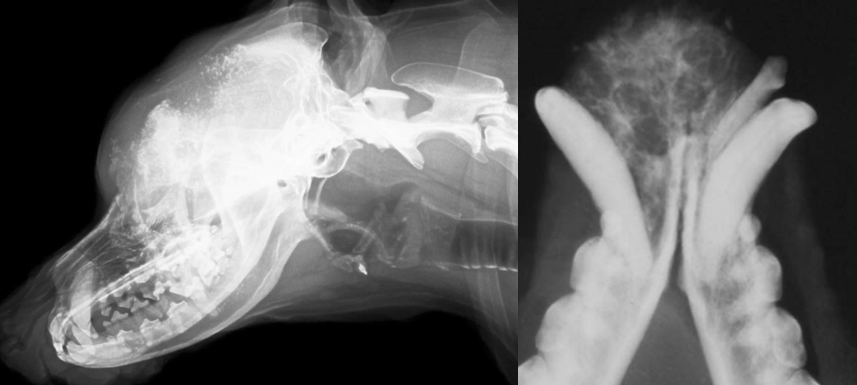

19

Q

identify pathology

A

calvarium neoplasia in left image

mandibular neoplasia in right side image